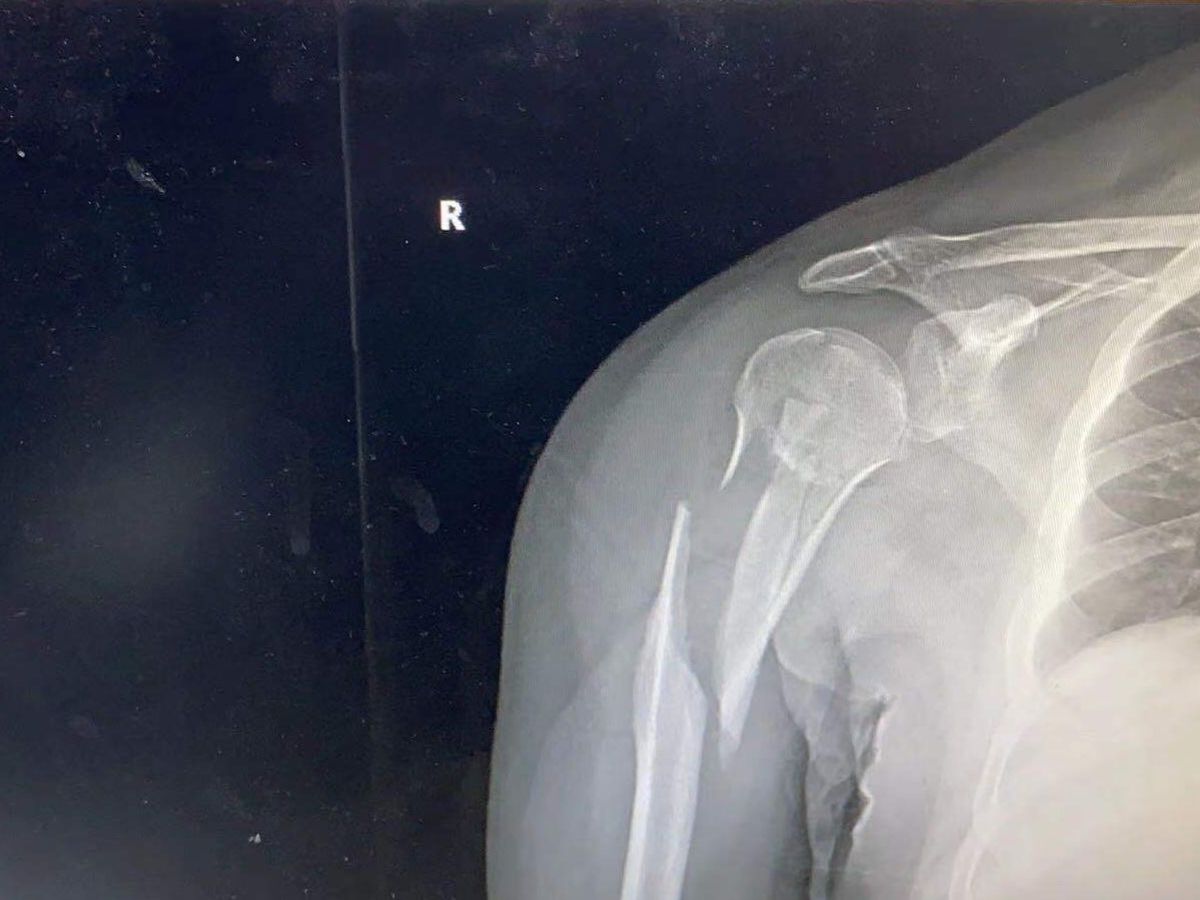

I am in Shanghai China and a hit and run driver accident from rear on my bicycle cause severe break to my right arm. I am a professional drummer but i may not be able to perform for several months. I don’t have insurance and the operation is $10,000.